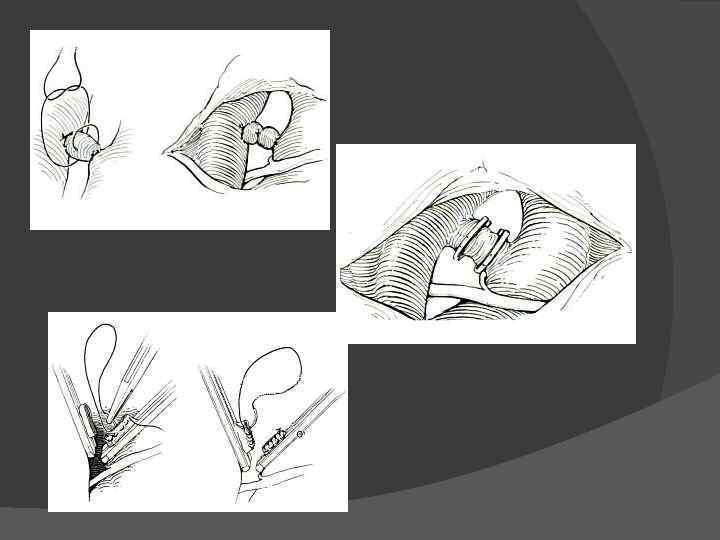

Лечение Спонтанное закрытие артериального протока наблюдается довольно редко. Как правило, оно происходит через боталлинит. Поэтому в настоящее время во всех случаях такого порока считается показанным оперативное лечение. Из левосторонней задне-боковой торакотомии перевязывают проток двумя-тремя лигатурами , клипируют или пересекают его с последующим прошиванием и перевязкой обеих культей.